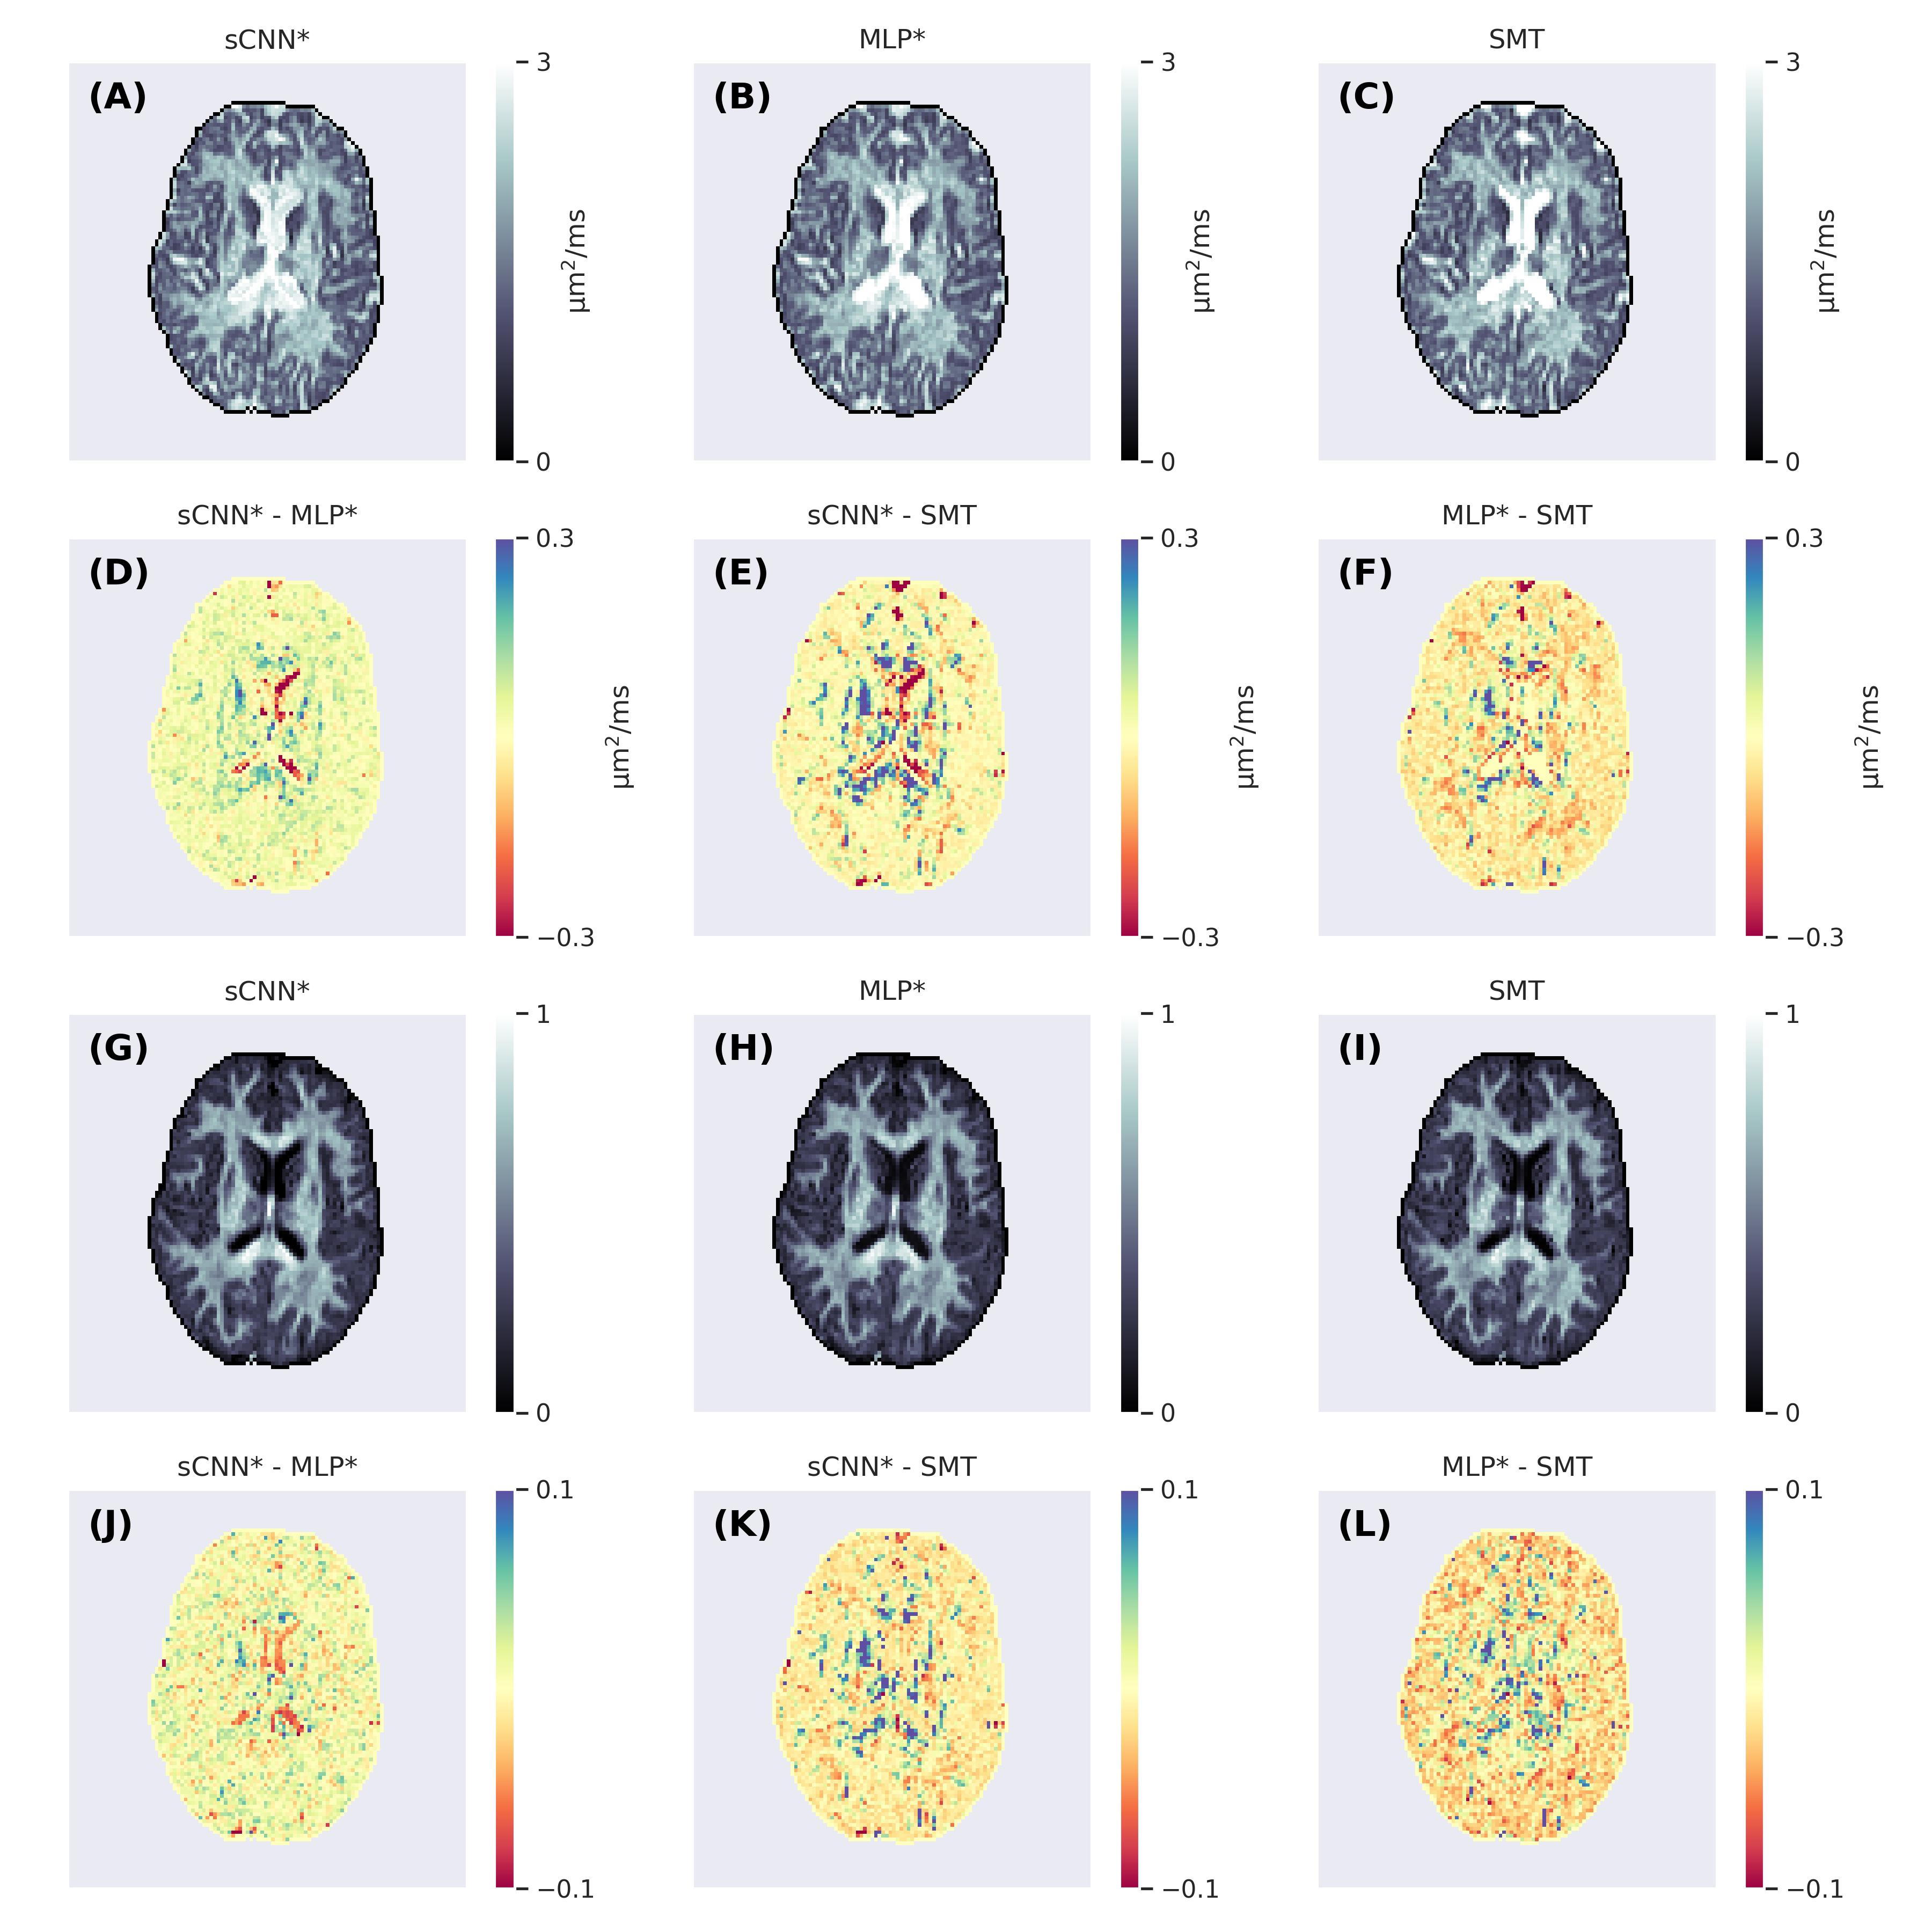

Figure 3 shows parameter maps generated using the three methods. The maps produced by the ML-based methods appear less noisy. Overall, the sCNN estimated d𝑑ditalic_d to be greater than the MLP (mean difference = 2.41022.4superscript1022.4\cdot 10^{-2}2.4 ⋅ 10 start_POSTSUPERSCRIPT - 2 end_POSTSUPERSCRIPT µm22{}^{2}start_FLOATSUPERSCRIPT 2 end_FLOATSUPERSCRIPT/ms; std of difference = 8.11028.1superscript1028.1\cdot 10^{-2}8.1 ⋅ 10 start_POSTSUPERSCRIPT - 2 end_POSTSUPERSCRIPT µm22{}^{2}start_FLOATSUPERSCRIPT 2 end_FLOATSUPERSCRIPT/ms) and SMT (mean difference = 0.91020.9superscript1020.9\cdot 10^{-2}0.9 ⋅ 10 start_POSTSUPERSCRIPT - 2 end_POSTSUPERSCRIPT µm22{}^{2}start_FLOATSUPERSCRIPT 2 end_FLOATSUPERSCRIPT/ms; std of difference = 12.710212.7superscript10212.7\cdot 10^{-2}12.7 ⋅ 10 start_POSTSUPERSCRIPT - 2 end_POSTSUPERSCRIPT µm22{}^{2}start_FLOATSUPERSCRIPT 2 end_FLOATSUPERSCRIPT/ms). However, in the CSF the sCNN tended to estimate d𝑑ditalic_d to be less than the MLP or SMT. Overall, the sCNN estimated f𝑓fitalic_f to be greater than the MLP (mean difference = 0.51020.5superscript1020.5\cdot 10^{-2}0.5 ⋅ 10 start_POSTSUPERSCRIPT - 2 end_POSTSUPERSCRIPT; std of difference = 3.61023.6superscript1023.6\cdot 10^{-2}3.6 ⋅ 10 start_POSTSUPERSCRIPT - 2 end_POSTSUPERSCRIPT) and SMT (mean difference = 0.11020.1superscript1020.1\cdot 10^{-2}0.1 ⋅ 10 start_POSTSUPERSCRIPT - 2 end_POSTSUPERSCRIPT; std of difference = 4.51024.5superscript1024.5\cdot 10^{-2}4.5 ⋅ 10 start_POSTSUPERSCRIPT - 2 end_POSTSUPERSCRIPT) while exhibiting a similar yet lesser tissue-dependent pattern as d𝑑ditalic_d. Figure 4 shows example ODFs generated by the trained sCNN.

Figure 3: Axial slices of the intra-neurite diffusivity (A-C) and intra-neurite signal fraction (G-I) maps generated using the spherical convolutional neural network, multi-layer perceptron, and spherical mean technique. The second row (D-F) shows the differences between the intra-neurite diffusivity maps and the fourth row (J-L) shows the differences between the intra-neurite signal fraction maps.